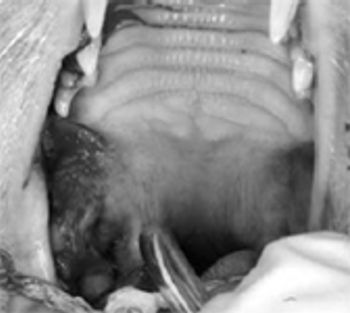

Benign and malignant masses are commonly encountered in the oral cavities of dogs and cats.